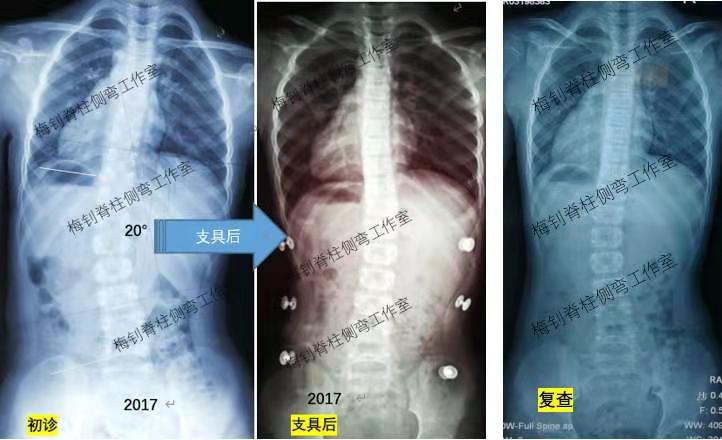

女孩,2017年发现侧弯,当年9岁,侧弯20度,穿戴支具后处于过矫状态。尽管支具效果不错,患儿身高也不断增长,但每隔半年拍片复查都会有大幅度反弹。好在患者家长听从我们的建议,坚持佩戴支具,今年2月,患儿脱支具30小时拍片,脊柱终于有所稳定,如下图:

总结:如果脱支具后脊柱反弹较大,要检查支具有没有问题,如果支具没有问题就需要坚持穿戴,在支具的引导和脊柱的不断生长下,相信脊柱终会有可喜的变化。脊柱侧弯、脊柱侧弯、脊柱侧弯